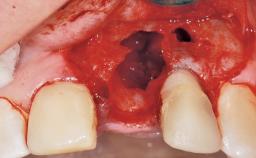

A 29-year-old female patient presented for treatment to replace the upper left central incisor tooth with an implant- supported restoration. The tooth had been intermittently symptomatic for the previous 12 months. The tooth had originally suffered trauma about 15 years previously. Several endodontic treatments had been performed, including an apicectomy procedure to retain the tooth. The patient was healthy and a non-smoker. She had reasonable expectations in regard to esthetic outcomes and the risk of marginal tissue recession following treatment. At medium smile, the gingival margins of the upper teeth were visible, with a display of 3 to 4 mm of the gingival margins. Gingival recession of tooth 21 and a discrepancy in the gingival levels between teeth 11 and 21 was observable during normal speech and smile.